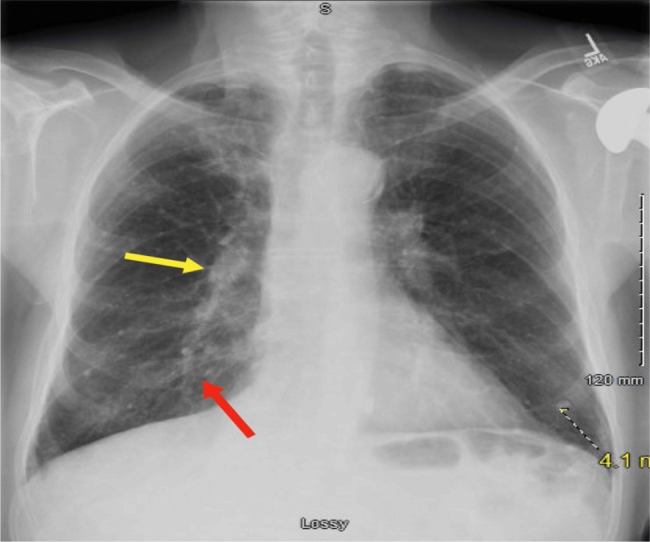

Case description: We present a case of a 78-year-old male with CLL receiving chemotherapy, who developed burning pain in the tongue and oral mucosa, accompanied by a non-productive cough. He was initially diagnosed with pneumonia, but further investigation revealed co-infection involving M. avium and S. apiospermum.

Discussion: The coexistence of M. avium and S. apiospermum underscores the complexity of infectious complications in CLL. The patient's chemotherapy was halted due to active pneumonitis observed on imaging in order to improve his leukocyte count. Antifungal therapy was not initiated due to a lack of evidence of invasive fungal infection. Antimycobacterial therapy for M. avium complex was initiated.